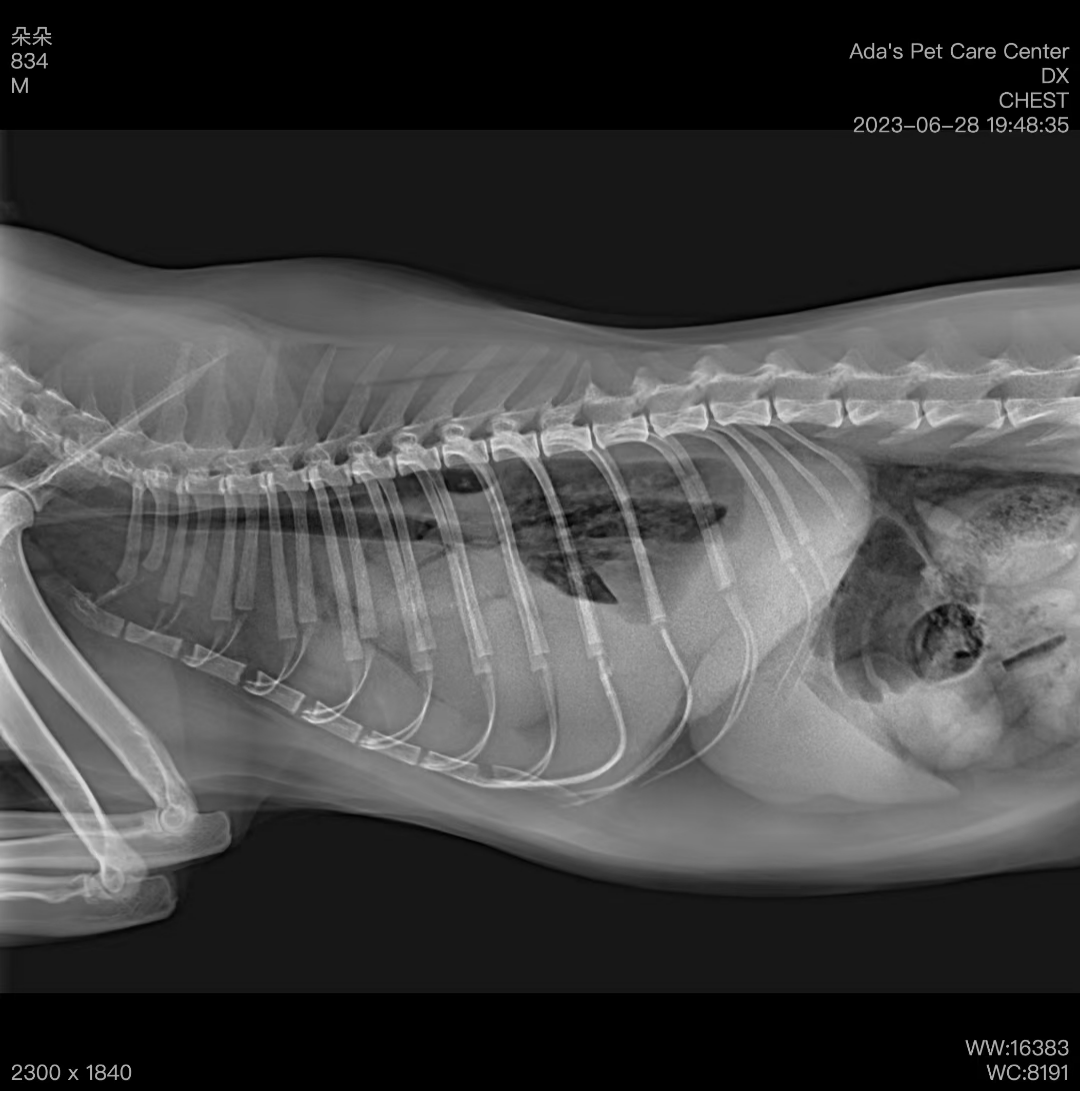

Case OverviewXiao Li Hua is a 4-year-old Chinese tabby cat who came to us with sudden difficulty breathing and shortness of breath. After some tests, we diagnosed it with chylothorax. We started with a staged treatment plan, and after surgery, the cat mad

Recently, our clinic treated an emergency pet, Nana, who suddenly exhibited symptoms such as rapid breathing, poor exercise tolerance, and lethargy. These signs didn’t seem like typical minor illnesses, so we immediately performed a thorough examination.I